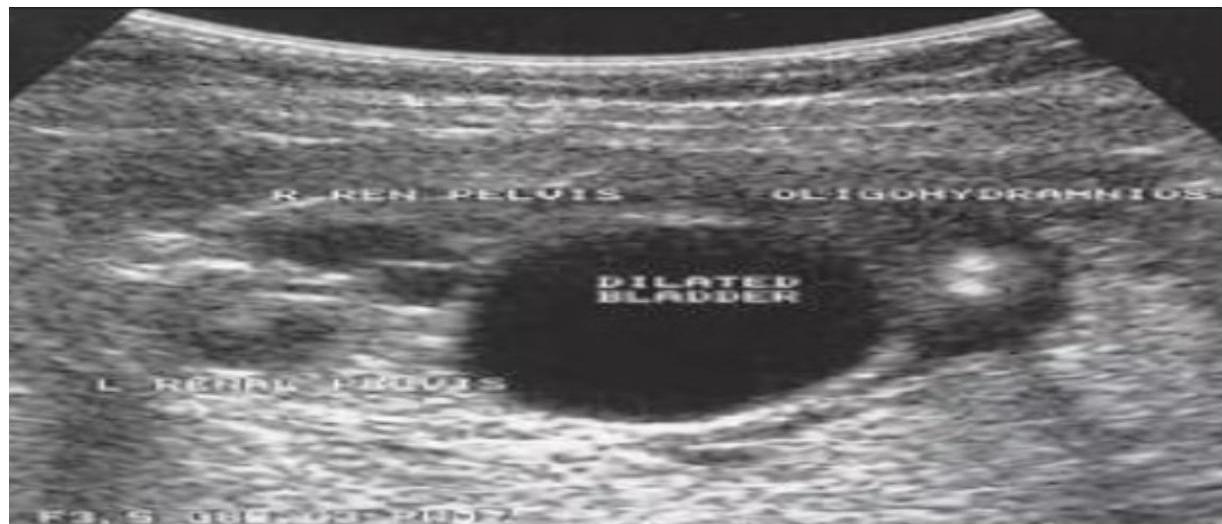

Antenatal ultrasound – Antenatal ultrasound showing urinary outflow obstruction from posterior urethral valve, with characteristic findings of dilated posterior urethra, thickened bladder wall, and bilateral hydronephrosis.